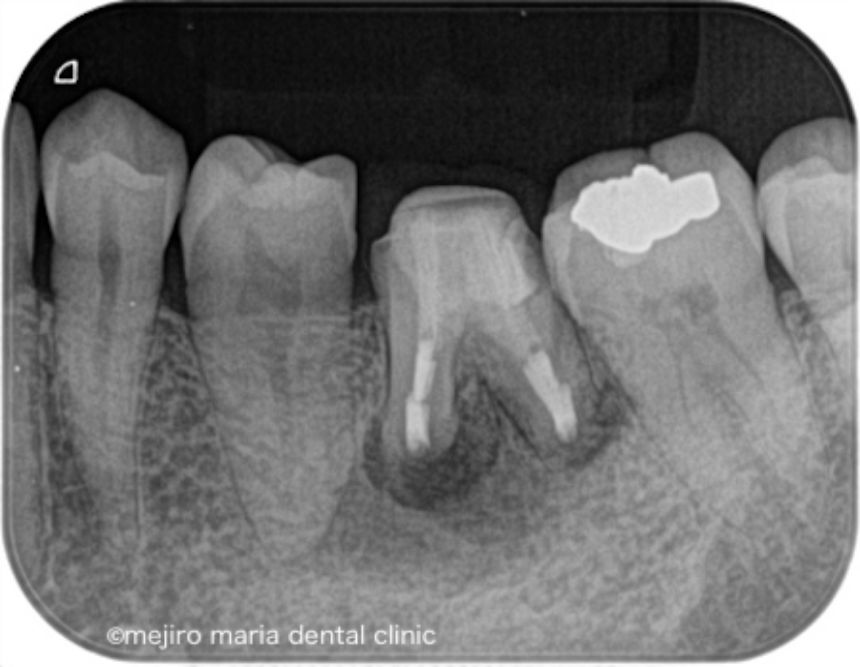

当院にて根管治療を開始するも根管治療の反応は乏しく、術前に確認できていた症状の改善は認められませんでした。その為、この患者様には歯根端切除術を追加で行い、マネージメントをさせていただくこととなりました。

歯根端切除術時に根尖を3mmほど切断したところ、根尖を取り囲むほどの歯石が確認され、この歯石の感染が根尖性歯周炎の治癒を妨げていた可能性がありました(写真)。

術後3ヶ月の経過観察では、歯肉の腫れや噛んだときの違和感、痛みは消失し予後良好と判断しました。引き続き最終補綴処置(被せ物)の製作を行い2年間の経過観察に移行することとなりました。